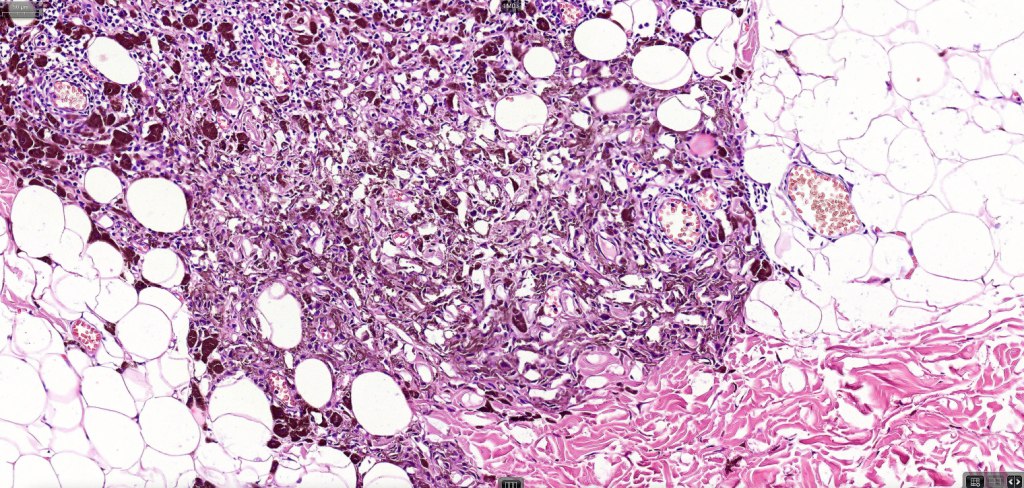

3. a deep penetrating nevus like lesion showing obvious signs of malignancy including greater pleomorphism than is usually seen combined with excessive mitotic activity, deep mitoses and atypical forms

4. melanoma which shows a deep penetrating architecture although the cytology remains epithelioid throughout